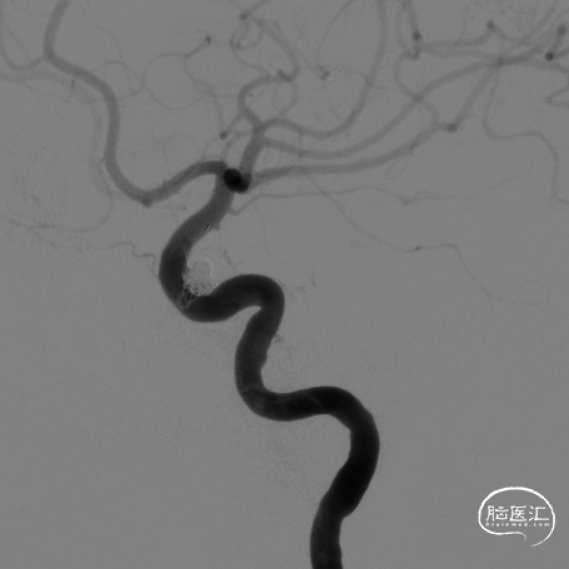

行标准正侧位造影发现动脉瘤无显影,载瘤动脉及远端分支血管通畅。股动脉造影后,撤出导引导管,拔除鞘管,Angio-Seal 1枚缝合血管穿刺点。病人术后麻醉清醒安返监护病房。